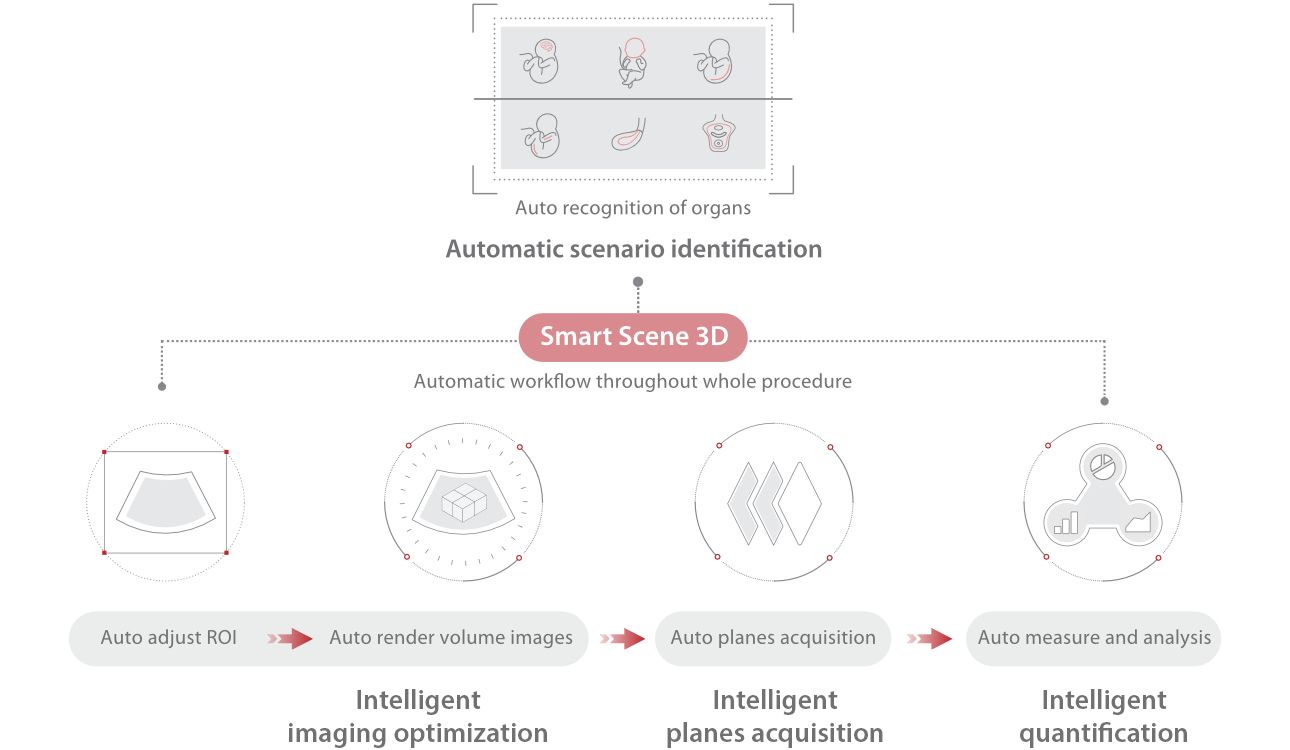

Nuewa I9 Elite Edition ├© progettato appositamente per l'assistenza sanitaria a donne e neonati e offre un'esperienza innovativa sviluppata sulla base di conoscenze approfondite relative a scenari clinici complessi, per risposte accurate e tempestive, nonch├® un'efficienza e un'esperienza utente eccezionali